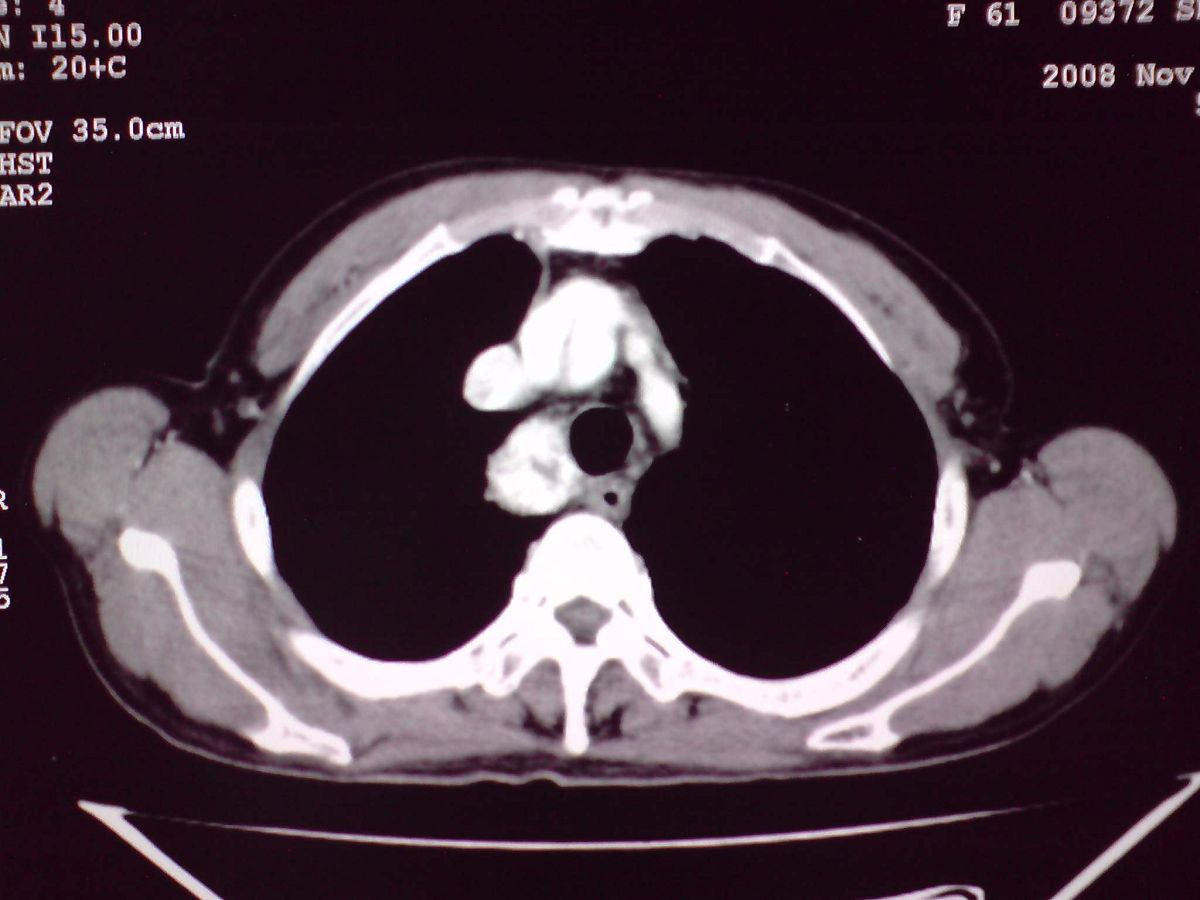

患者女性,65岁,无明显不适,甲状腺功能无异常

结节状甲状腺肿,部分突入胸腔,形成胸内甲状腺

胸内甲状腺伴结节性甲状腺肿!因病灶明显钙化很难排除:甲状腺癌可能性!建议穿刺活检!

双侧甲状腺肿大,向下部分突入胸腔,双侧甲状腺内密度不均,可见结节状低密度影,并见散在斑点状钙化,增强后病灶实性部分强化明显,气管受压稍变窄左移。

考虑:双侧甲状腺腺瘤可能,不除外甲状腺癌。

甲状腺左右叶增大,并向下突入胸腔内,其内可见多发条片状钙化影及囊性低密度影,邻近组织及血管无浸润、包埋征像,双侧结节性甲状腺肿伴右侧甲状腺腺瘤形成可能性大,甲状腺癌待排;因病人就要手术,期待结果。